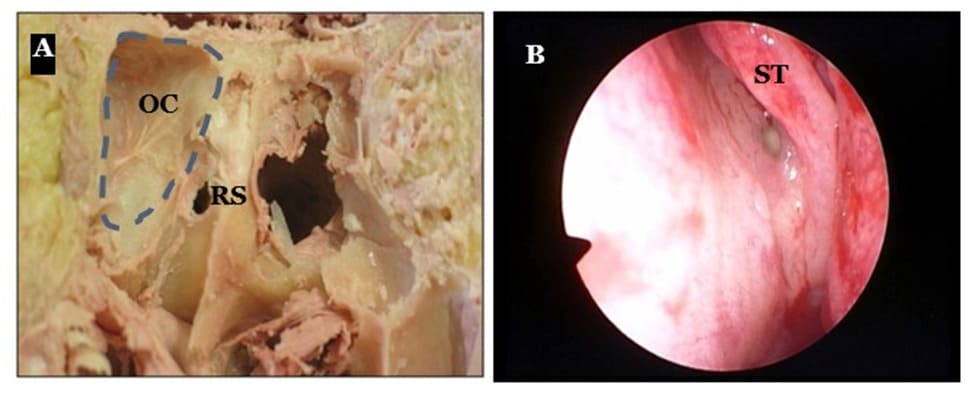

The Onodi cell (OC) is the most posterior and lateral ethmoidal cell. It has important relationships with the optic nerve, which is lateral and superior to it. The sphenoid sinus is situated more medially, inferiorly and posteriorly (3,7).

Each sphenoid sinus communicates with the nasal cavity by means of an aperture in the upper part of the anterior wall. This aperture, also called an ostium, is situated at the junction of the superior third and the two inferior thirds of the anterior wall of the sphenoid sinus. The superior turbinate is the best surgical landmark to identify the natural ostium. It separates the sphenoethmoidal recess and the posterior ethmoid (8). In 85% of cases the ostium is situated medially to the posterior end of the superior turbinate (ST), in the sphenoethmoidal recess. In 15% of cases, it is situated lateral to the tail of the ST (9-11).

Figure 2:(A) The Onodi cell (OC) and the Rostrum Sphenoidale (RS) on a cadaver. (B) Endoscopic view showing the ostium of the sphenoid sinus along the tail of the superior turbinate - left side.